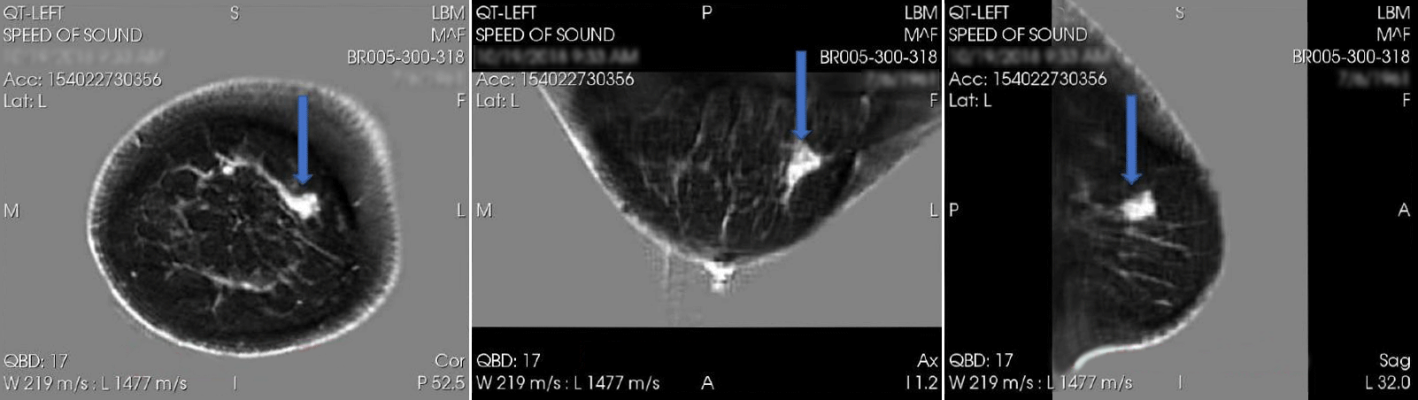

April 16, 2024 — QT Imaging Holdings, Inc., a medical device company engaged in research, development, and commercialization of innovative body imaging systems, announced positive data regarding the diagnostic performance of QTI’s Breast Acoustic CT Scans for mass detection from its second blinded multi-reader multi-case study. The study was published in Academic Radiology, online, in January 2024: A Multireader Multicase (MRMC) Receiver Operating Characteristic (ROC) Study Evaluating Noninferiority of Quantitative Transmission (QT) Ultrasound to Digital Breast Tomosynthesis (DBT) on Detection and Recall of Breast Lesions - Academic Radiology

Twenty-four breast radiologists participated in a study of 177 selected cases (66 with cancer, atypia, or solid mass and 111 normal or with nonsolid benign abnormality). The study found that QTI’s Breast Acoustic CTTM is similarly effective as digital breast tomosynthesis (DBT), also known as 3D mammography, in that the area under receiver operating characteristic curve (AUC) was statistically non-inferior for QTI scan compared with DBT for the AUC difference margin of -0.05. This means that QTI technology is non-inferior to DBT in the detection of breast lesions as a whole, with high specificity in determining benign cysts and thus decreasing benign recall rates. Statistical analysis was performed by Dr. Yulei Jiang from the Department of Radiology of the University of Chicago.